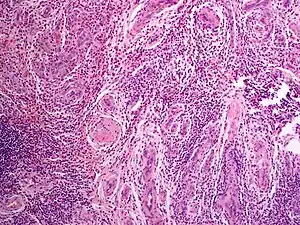

| Angiolymphoid hyperplasia with eosinophilia | |

Angiolymphoid hyperplasia with eosinophilia (also known as:[1] "Epithelioid hemangioma," "Histiocytoid hemangioma," "Inflammatory angiomatous nodule," "Intravenous atypical vascular proliferation," "Papular angioplasia," "Inflammatory arteriovenous hemangioma," and "Pseudopyogenic granuloma") usually presents with pink to red-brown, dome-shaped, dermal papules or nodules of the head or neck, especially about the ears and on the scalp.[2]